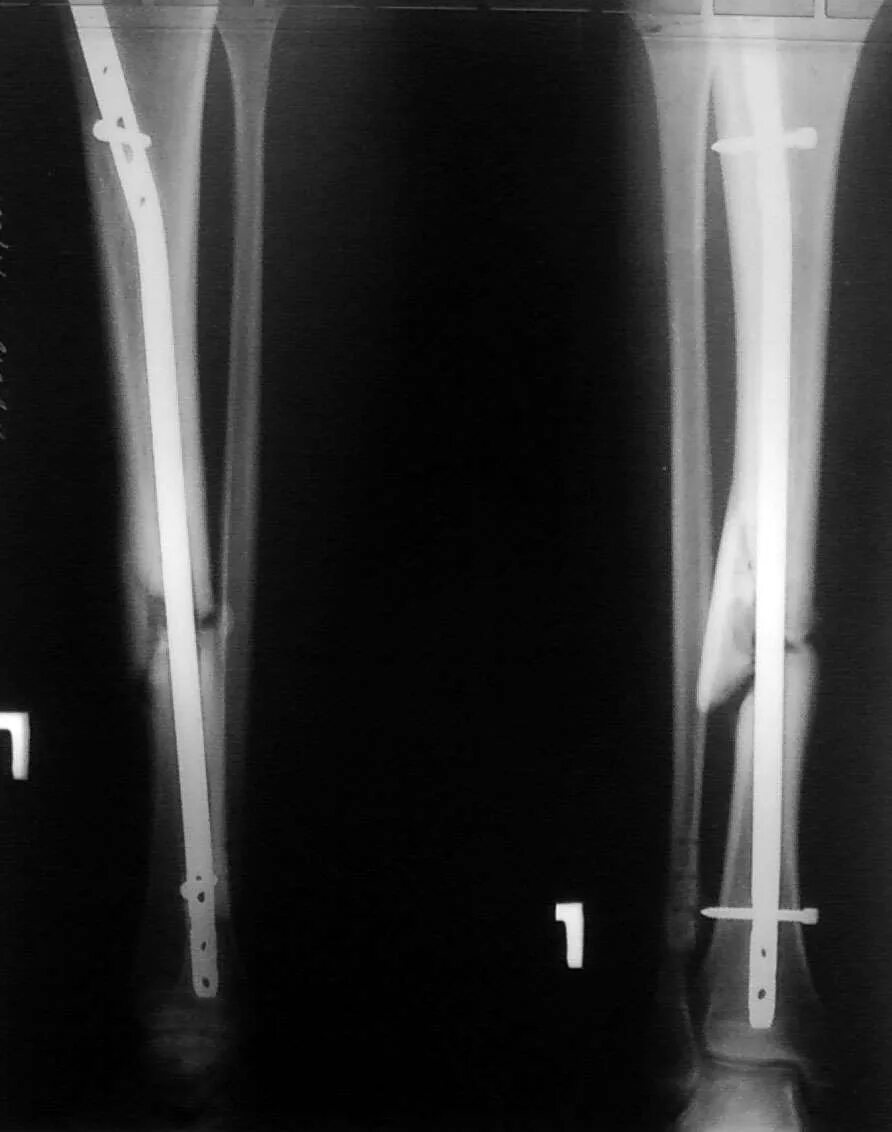

Сколько срастается перелом берцовой